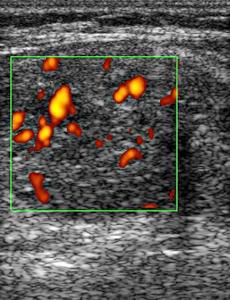

Цветная допплеровская картография позволяет ультразвуковому аппарату отображать направления движения частиц с помощью цвета. Частицы, движущиеся в одну сторону, окрашиваются в красный цвет, а в противоположную – в синий. Этот метод допплеровского исследования помогает, во-первых, отличить сосуды от кистозных образований или других тёмных участков, во-вторых, определить направление кровотока в сосудах, в-третьих, выявить ткани с повышенной сосудистой активностью (например, при аутоиммунном тиреоидите или диффузном токсическом зобе) и узлы с показателями избыточной функции или онкологических поражений (таких как токсические аденомы или злокачественные узлы щитовидной железы). Регистрация повышенного кровотока в лимфатических узлах на шее может указывать на метастазы рака щитовидной железы.

Энергетическая допплерография демонстрирует общее количество движущихся частиц, отражая интенсивность кровотока в исследуемом участке. На энергетическом допплеровском исследовании интенсивность покажется разными оттенками красного — от оранжевого до коричневого. Этот метод используется для уточнения результатов в случае неясности после цветного допплера.

Одним из важных аспектов опухоли является уровень васкуляризации или кровоснабжения узла. Большинство злокачественных узлов характеризуются выраженной васкуляризацией, хотя существуют также и аваскулярные (бескровные) образования. Более того, активная васкуляризация встречается и в функционирующих (токсических) узлах, которые часто оказываются коллоидными, а не злокачественными. Таким образом, данное ультразвуковое исследование недостаточно для окончательного постановления диагноза, и выявление потенциально опасных узлов должно осуществляться лишь врачом-сонографистом.